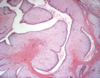

What is this showing?

There is a very pink epithelium characteristic of a nonproliferative cyst. Frequently, the lining cells are large and polygonal with eosinophilic cytoplasm, a process called apocrine metaplasia which is virtually always benign